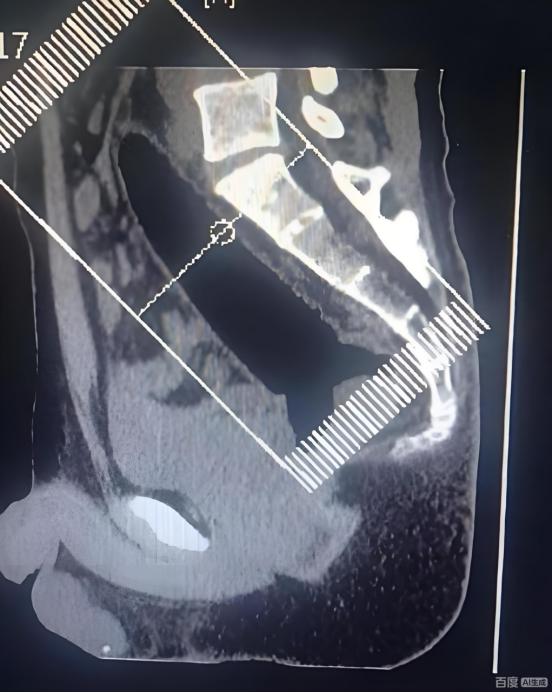

太离谱了!河南郑州,一男子捂着屁股去医院肛肠科看病,可问诊时,男子却扭扭捏捏说屁股卡了一个东西,开始医生还以为问题不大,可看了才发现,这哪是卡了东西,一根异物已深入直肠,最后手术后取出一根22厘米异物。网友:这是个狠人!   “有东西......卡在我下面了......”男子疼的冷汗都冒出来了,也抵消不了内心的羞耻与尴尬,他坐在肛肠科的诊室里,双手紧紧夹着腿,头几乎埋进胸口。   面对医生一遍遍耐心的询问,他才支支吾吾说出了症状:“就是……一个玩具,拔不出来了。”   其实也没什么不好意思的,就是事发当天,26岁的年轻人小陈(化姓)想在家放松一下,没想到手一滑,一根硅胶成人用品直接滑进了肛门。   起初,小陈他尝试自己解决,用手抠、用工具夹,甚至忍着痛蹲了好久,可那东西不但没出来,反而越陷越深。   越发剧烈的胀痛和隐隐的恐惧终于让他意识到:这事靠自己搞不定。可真要走进医院,他又实在拉不下脸。就这样自己在家犹犹豫豫了好几个小时,直到疼得坐不住了,才咬牙挂了急诊。   然而,接诊医生检查后也是吓出一身冷汗。原来在小陈耽误的那几个小时里,异物已经完全进入直肠深处,手指根本摸不到头;并且异物是透明硅胶材质,X光片成像也不清晰,为今之计,只能通过手术取出了。   好在手术过程还算顺利,最终取出了一根长达22厘米的硅胶棒。现场医护人员都忍不住倒吸一口凉气:这尺寸,别说取出,光是进去就让人难以想象。   万幸的是,患者肠道没有穿孔,也没有感染,术后观察两天就可以出院了。   这事说来确实有些难以启齿,我们就不过多探讨原因了。重要的是想借此提醒大家:成年人有生理需求很正常,但要注意方式方法。   小陈的这波操作,是一种风险极高的行为,绝不可取。人体的直肠黏膜非常娇嫩,肠道也有自然的生理弯曲,这不仅会让异物难以自行排出,更容易在过程中造成不可逆的损伤。   要知道,身体不是探索未知的试验场,它的承受能力有清晰的边界。任何快感,都不应该以牺牲健康和安全为代价。   对此你有什么看法?欢迎在评论区留言讨论。成人用品 身体构造   信息来源: 周道新闻2026-1-14|男子不慎将22厘米玩具滑入肛取不出,医生看了都摇头。 文|墨海 编辑|史叔